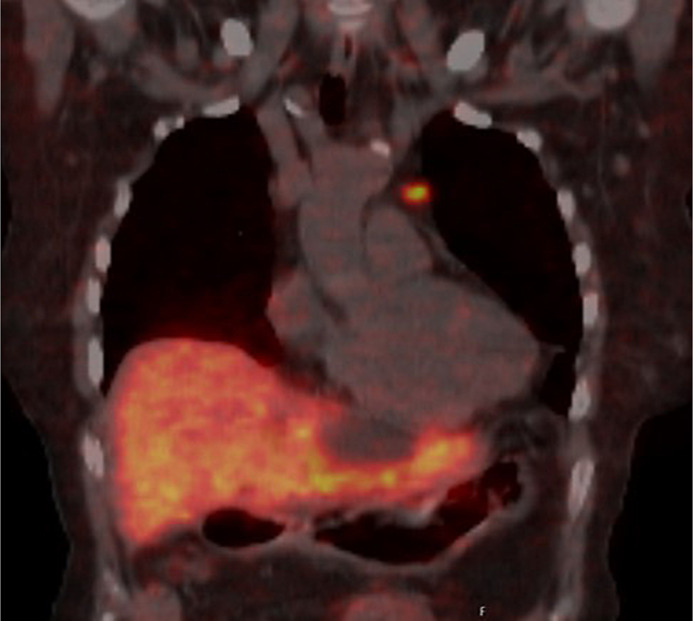

Summary: This review discusses the pathophysiology, types, clinical presentation, diagnosis, and management of NETs that ectopically secrete CRH and ACTH. Particular emphasis is placed on the importance of identifying dual CRH/ACTH secretion, which complicates diagnosis and treatment. Furthermore, the review highlights the prognosis, common complications, and future directions for research in this area. We further report the case of a 53-year-old female patient who presented with severe Cushing's syndrome and was diagnosed with ectopic ACTH syndrome. Despite initial findings suggesting pituitary-dependent hypercortisolism, further investigations revealed the presence of a highly differentiated, atypically located tumor in the lung. Immunohistochemistry of the tumor tissue demonstrated not only ACTH but also CRH and CRH-R1 expression. The simultaneous expression of these molecules supports the hypothesis of a positive endocrine feedback loop within the NET, in which the release of CRH stimulates ACTH expression via binding to CRH-R1.